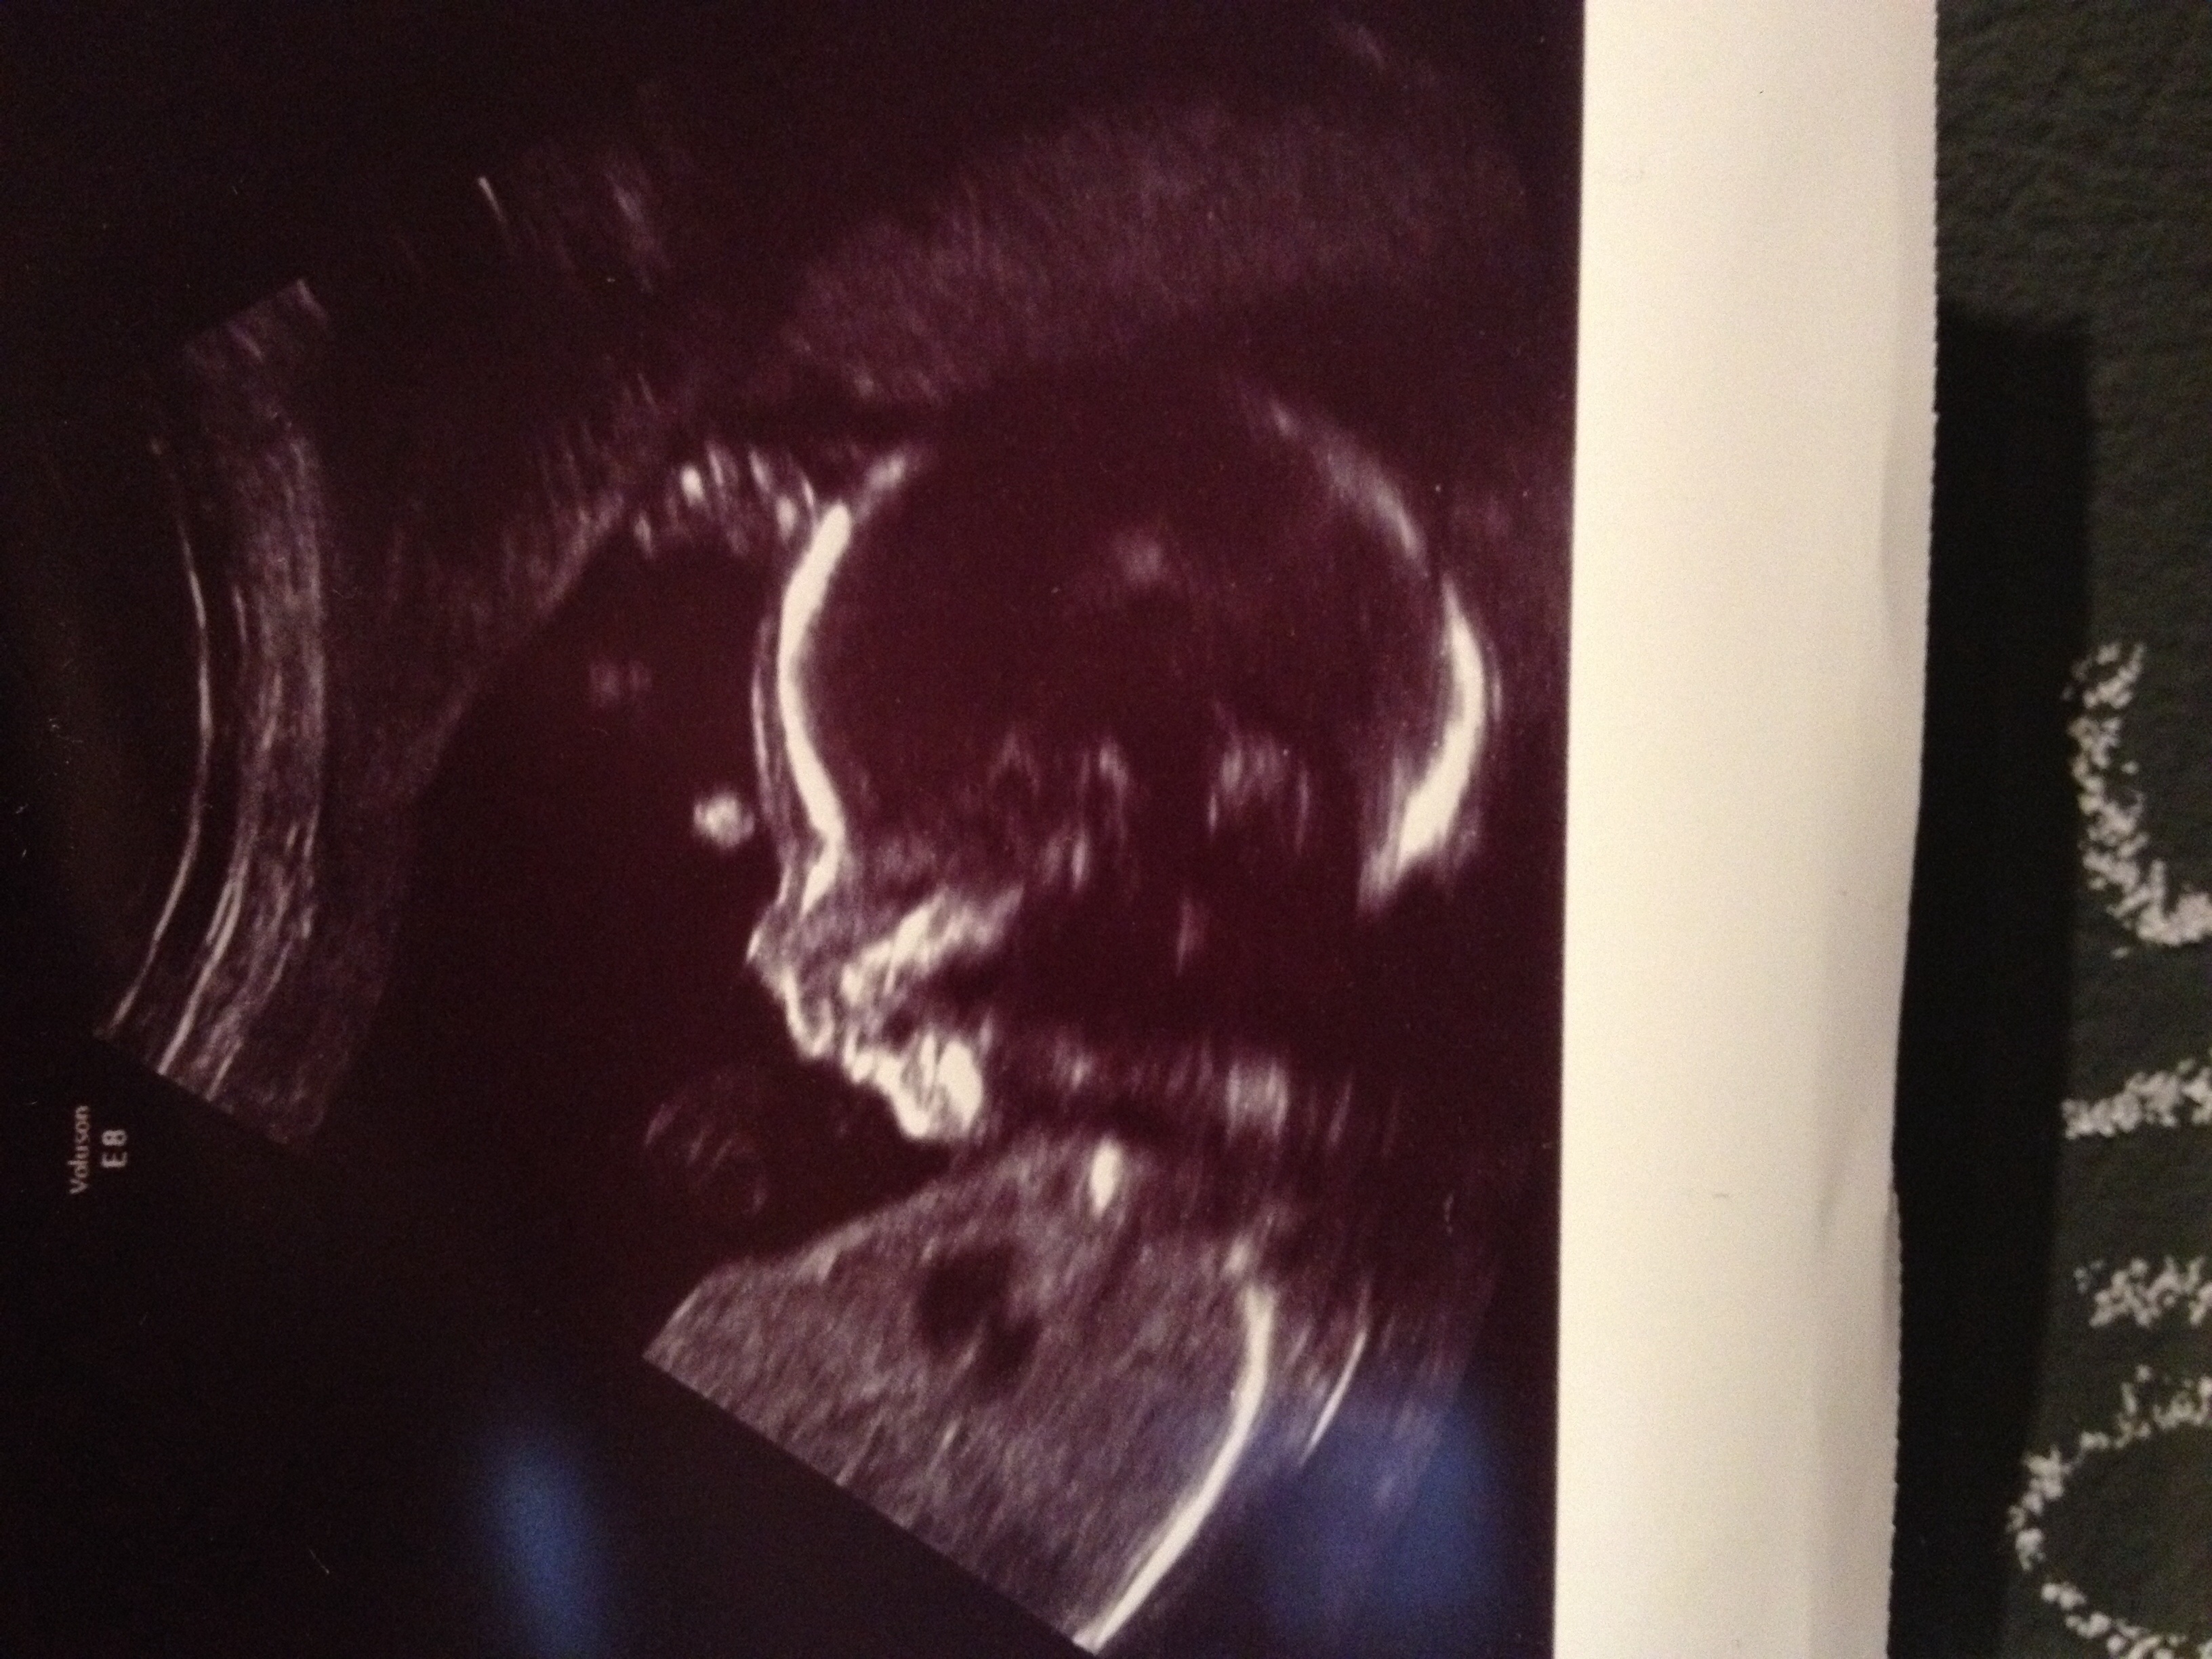

Here is our baby girl last Thursday at our a/s appointment. They found a cyst on her brain called Choroid Plexus Cyst so we have to see a perinatologist to have it looked at further to see if she possibly has Downs Syndrome since it is considered a soft marker. Dr was very positive about the outcome and said she had no other markers and that normally go away but it's just a precaution. Praying for the best! She just started kicking away a few days back and hubby has got to feel her twice already each on a different day. She is also sitting breech for now so hoping she uses the next 19 weeks to get into position : D